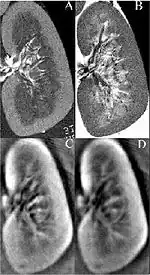

Thermoacoustic imaging was originally proposed by Theodore Bowen in 1981 as a strategy for studying the absorption properties of human tissue using virtually any kind of electromagnetic radiation.[1] But Alexander Graham Bell first reported the physical principle upon which thermoacoustic imaging is based a century earlier.[2] He observed that audible sound could be created by illuminating an intermittent beam of sunlight onto a rubber sheet. Shortly after Bowen's work was published, other researchers proposed methodology for thermoacoustic imaging using microwaves.[3] In 1994 researchers used an infrared laser to produce the first thermoacoustic images of near-infrared optical absorption in a tissue-mimicking phantom, albeit in two dimensions (2D).[4] In 1995 other researchers formulated a general reconstruction algorithm by which 2D thermoacoustic images could be computed from their "projections," i.e. thermoacoustic computed tomography (TCT).[5] By 1998 researchers at Indiana University Medical Center[6] extended TCT to 3D and employed pulsed microwaves to produce the first fully three-dimensional (3D) thermoacoustic images of biologic tissue [an excised lamb kidney (Fig. 1)].[7] The following year they created the first fully 3D thermoacoustic images of cancer in the human breast, again using pulsed microwaves (Fig. 2).[8] Since that time, thermoacoustic imaging has gained widespread popularity in research institutions worldwide.[9][10][11][12][13][14][15] As of 2008, three companies were developing commercial thermoacoustic imaging systems – Seno Medical,[16] Endra, Inc.[17] and OptoSonics, Inc.[18]